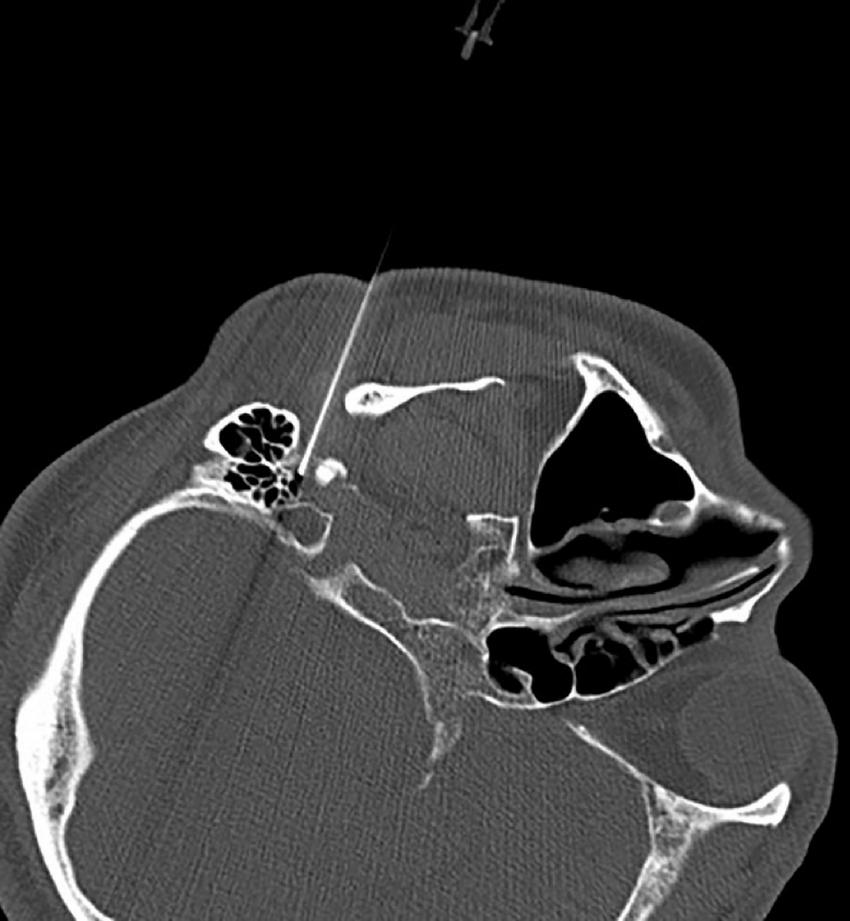

The CT layer with the stylomastoid foramen and without the bone barrier of the tympanic part of the temporal bone was selected as the puncture layer, and the CT measurement tool software was used to pull a straight line forward from the stylomastoid foramen. The intersection of the line and the skin is the puncture point (Figure 2). We determined the puncture depth (the distance from the puncture point to the target) and puncture angle (the angle between the puncture route and sagittal plane). After administering local anesthesia to the puncture site, a stylet 7-gauge radiofrequency needle with a length of 10 cm and an exposed end of 5 mm (Model 240100; Innomed Medical Technology Co., Ltd.) was gradually advanced toward the target under the guidance of intermittent CT inspection (Figure 3) and confirmed by three-dimensional reconstruction of CT scanning (Figure 4). The facial nerve was then stimulated with a radiofrequency probe at a frequency of 2 Hz and a current capacity of 0.5 mA (RF instrument model PMG230; Baylis Medical Co., Inc.). The positive facial muscle twitches from the stimulation indicated that the facial nerve was in close proximity (Supplementary Video 1).

FIGURE 3

Puncturing of the stylomastoid foramen under intermittent CT guidance.